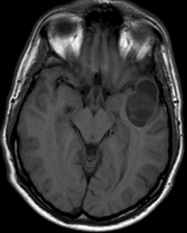

Un homme âgé de 33 ans, droitier, sans antécédents médicaux personnels ou familiaux, fut hospitalisé pour une crise d’épilepsie d’allure généralisée d’emblée. L’examen clinique, neurologique et général, était sans point d’appel.

L’IRM révéla l’existence d’une lésion tumorale, avec une double composante, kystique et charnue siégeant au niveau du lobe temporal gauche. La lésion apparaissait en hypo T1, en hyper T2 et Flair.